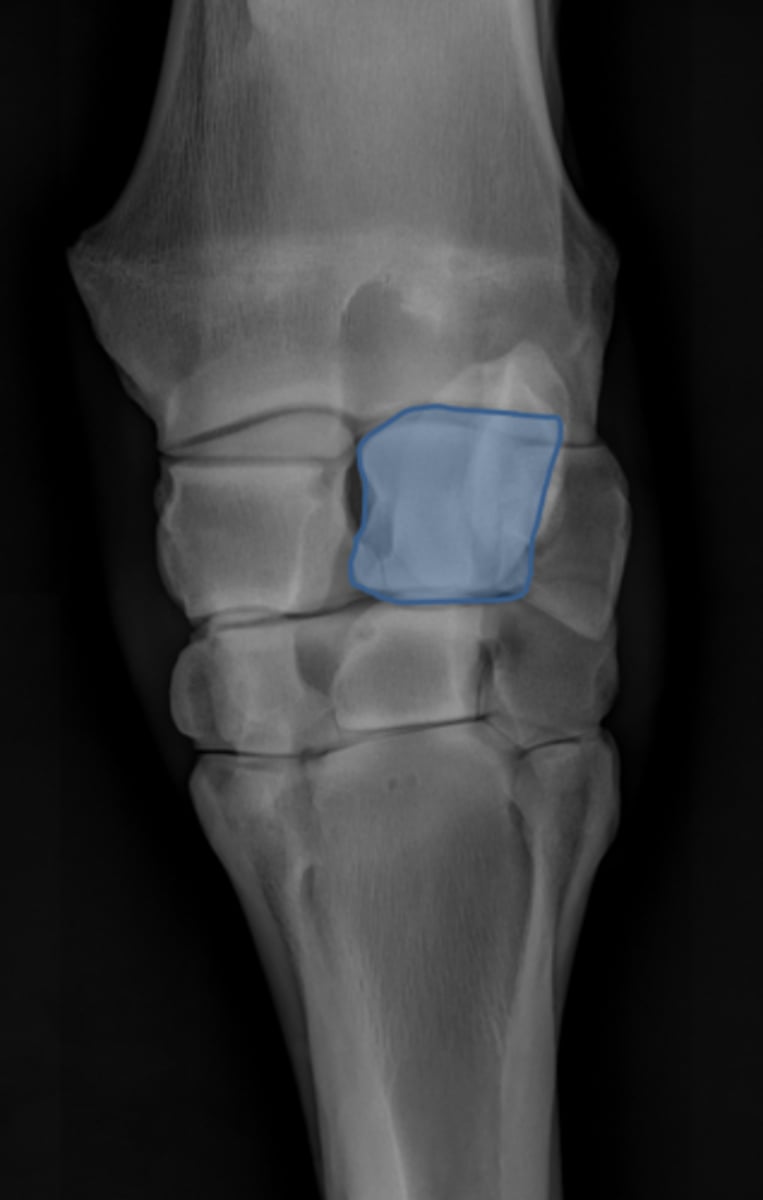

Carpus, lateral

ID joint and view

Antebrachiocarpal joint

Middle carpal joint

Carpometacarpal joint

Radial carpal bone

Intermediate carpal bone

Ulnar carpal bone

Third carpal bone

Second carpal bone

Fourth carpal bone

Accessory carpal bone

Second metacarpal (medial splint)

Fourth metacarpal (lateral splint)

Cannon bone

Carpus, DP

ID joint and view

Accessory carpal bone

Radial carpal bone

Intermediate carpal bone

Ulnar carpal bone

Second carpal bone

Third carpal bone

Fourth carpal bone

Second metacarpal (medial splint)

Third metacarpal

Fourth metacarpal (lateral splint)

DLPMO

ID view of carpus

Accessory carpal bone

Radial carpal bone

Intermediate carpal bone

Ulnar carpal bone

Second carpal bone

Third carpal bone

Fourth carpal bone